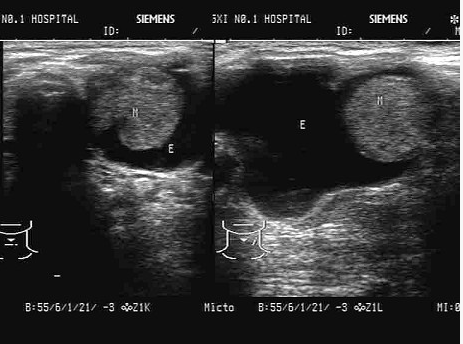

判断下图、彩图符合哪种眼睑疾病。

超声提示()。

A.眼睑神经纤维瘤

B.眼睑皮样囊肿

C.眼睑血肿

D.睑板腺癌